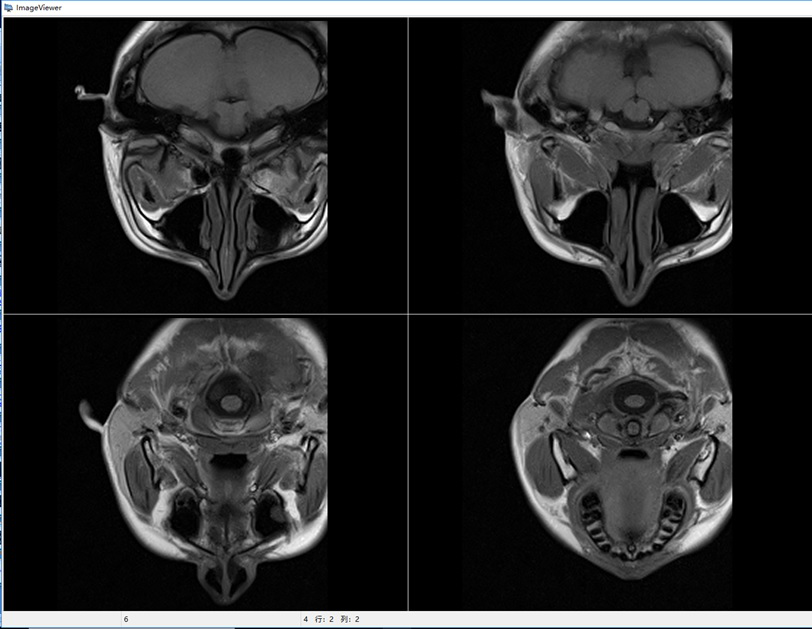

移動(dòng)式POCI磁共振成像儀屬于POCI(point of care imaging)成像裝備,也就是即時(shí)監(jiān)護(hù)成像,包括但不限于:神經(jīng)內(nèi)科和神經(jīng)外科的腦監(jiān)護(hù)成像、新生兒腦監(jiān)護(hù)、口腔醫(yī)學(xué)以及運(yùn)動(dòng)損傷監(jiān)護(hù)等,主要用于各類相關(guān)臨床醫(yī)院、科研機(jī)構(gòu)、研究型醫(yī)院,用于臨床診斷和疾病的動(dòng)物模型研究、認(rèn)知研究、新藥研發(fā)等。我們研發(fā)的移動(dòng)式POCI磁共振成像儀,采用了最新的輕量化永磁磁體技術(shù)和高效率的矩陣梯度技術(shù),使得整機(jī)具有更高的磁場強(qiáng)度、更低的使用成本、更好的成像效果和適用性。目前國內(nèi)MRI裝機(jī)量超過了11000臺(tái),而移動(dòng)式POCI磁共振成像儀目前國內(nèi)外還沒有成熟的產(chǎn)品。預(yù)計(jì)將來移動(dòng)式POCI磁共振成像儀的需求量接近全身MRI設(shè)備的需求,其總市場價(jià)值約有150億元,因此移動(dòng)式POCI磁共振成像儀具有良好的市場前景和經(jīng)濟(jì)效益。